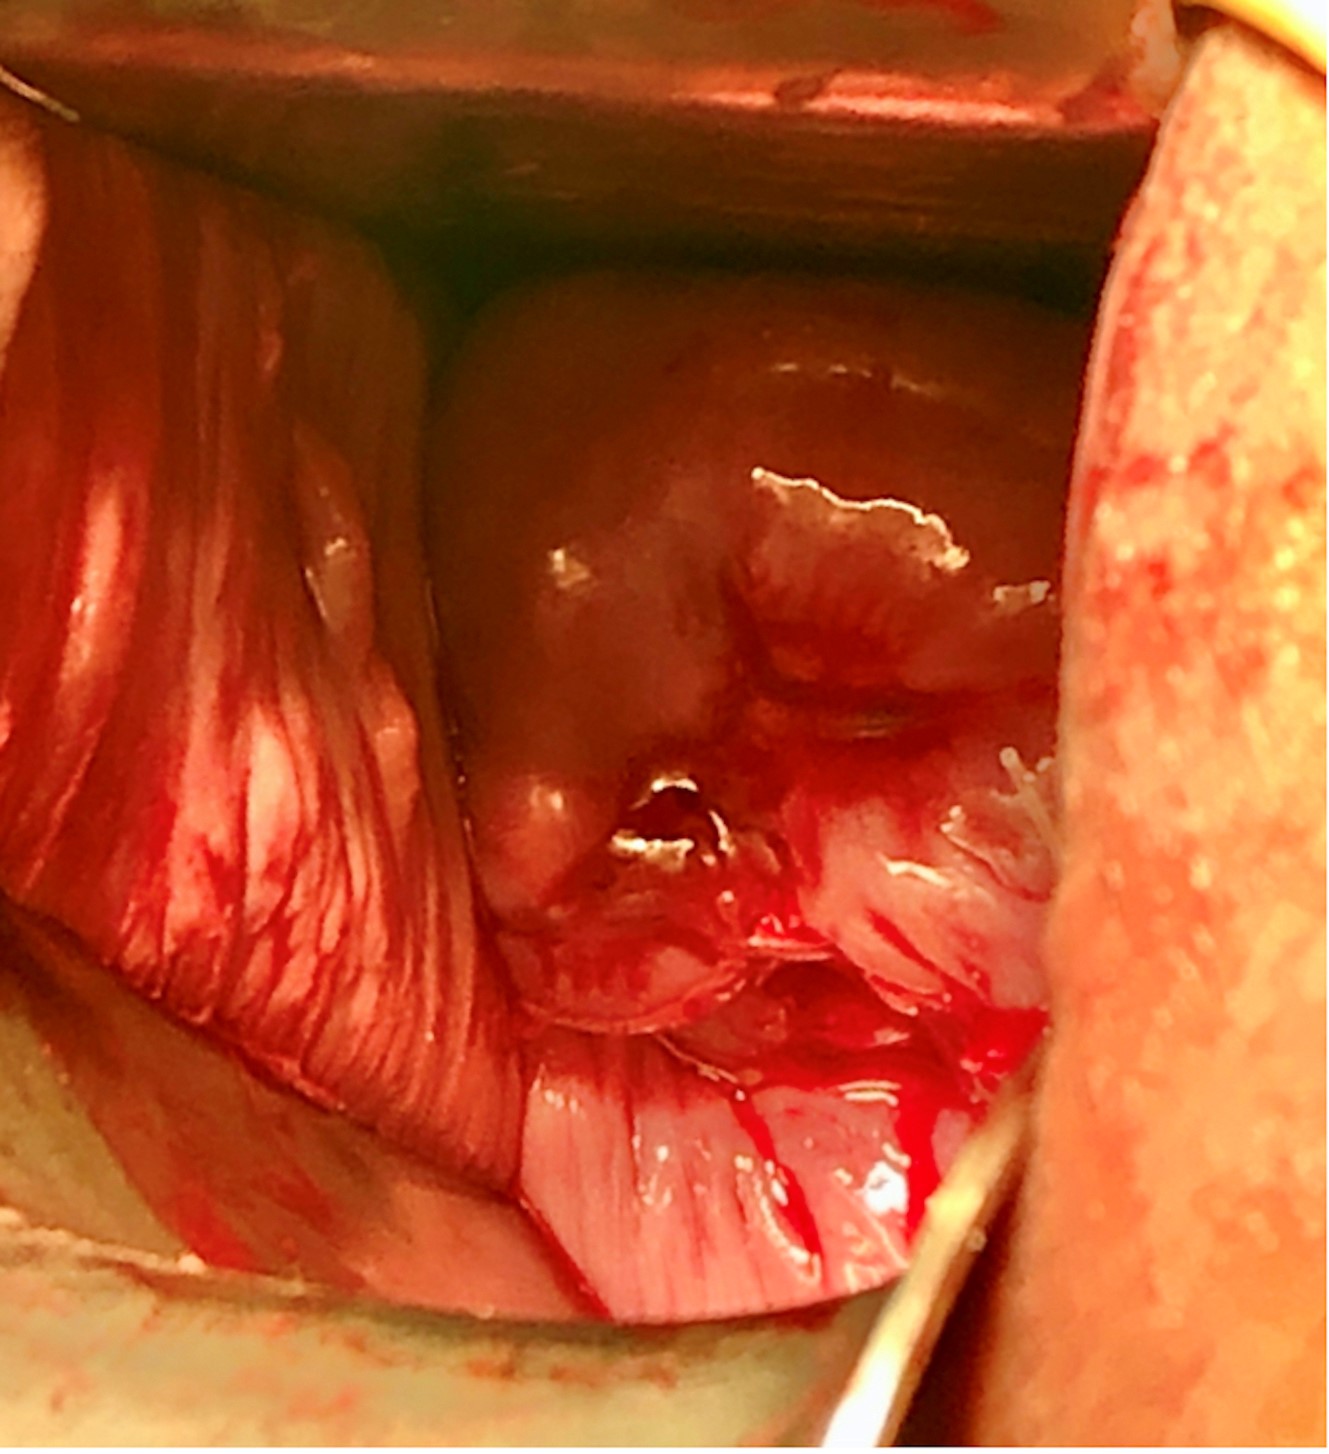

At admission, the patients underwent history taking, laboratory studies, fetal sonography (Fig. 1A), speculum examination (Fig. 1B), and tocodynamometry. Cervical cultures were collected in the lower genital tract. Rescue cerclage was performed under epidural anesthesia. Pre-operatively, prophylactic antibiotics were given, the bladder was emptied, and the vulva and vagina were sterilized with betadine solution, and then rinsed quickly with sterile saline to avoid irritation to the fragile amniotic membranes. In the Trendelenburg position, the operation started by reducing the protruding amniotic bag slowly and carefully with a large rinsed cotton swab until the effaced cervix could be visualized. A 16-French foley catheter was inserted into the uterine cavity with a balloon and gradually inflated while retrieving the cotton swab. The cervix was then grasped with Allis forceps at 0, 3, 6 and 9 o’clock positions. The McDonald suture was performed with one or two Mersilene tapes at the operator’s discretion (Fig. 2). The intrauterine Foley catheter was carefully deflated and removed while tying the tape(s).

Fig. 2.Speculum examination after reducing the amniotic sac and cerclage insertion for the same patient in Fig. 1.